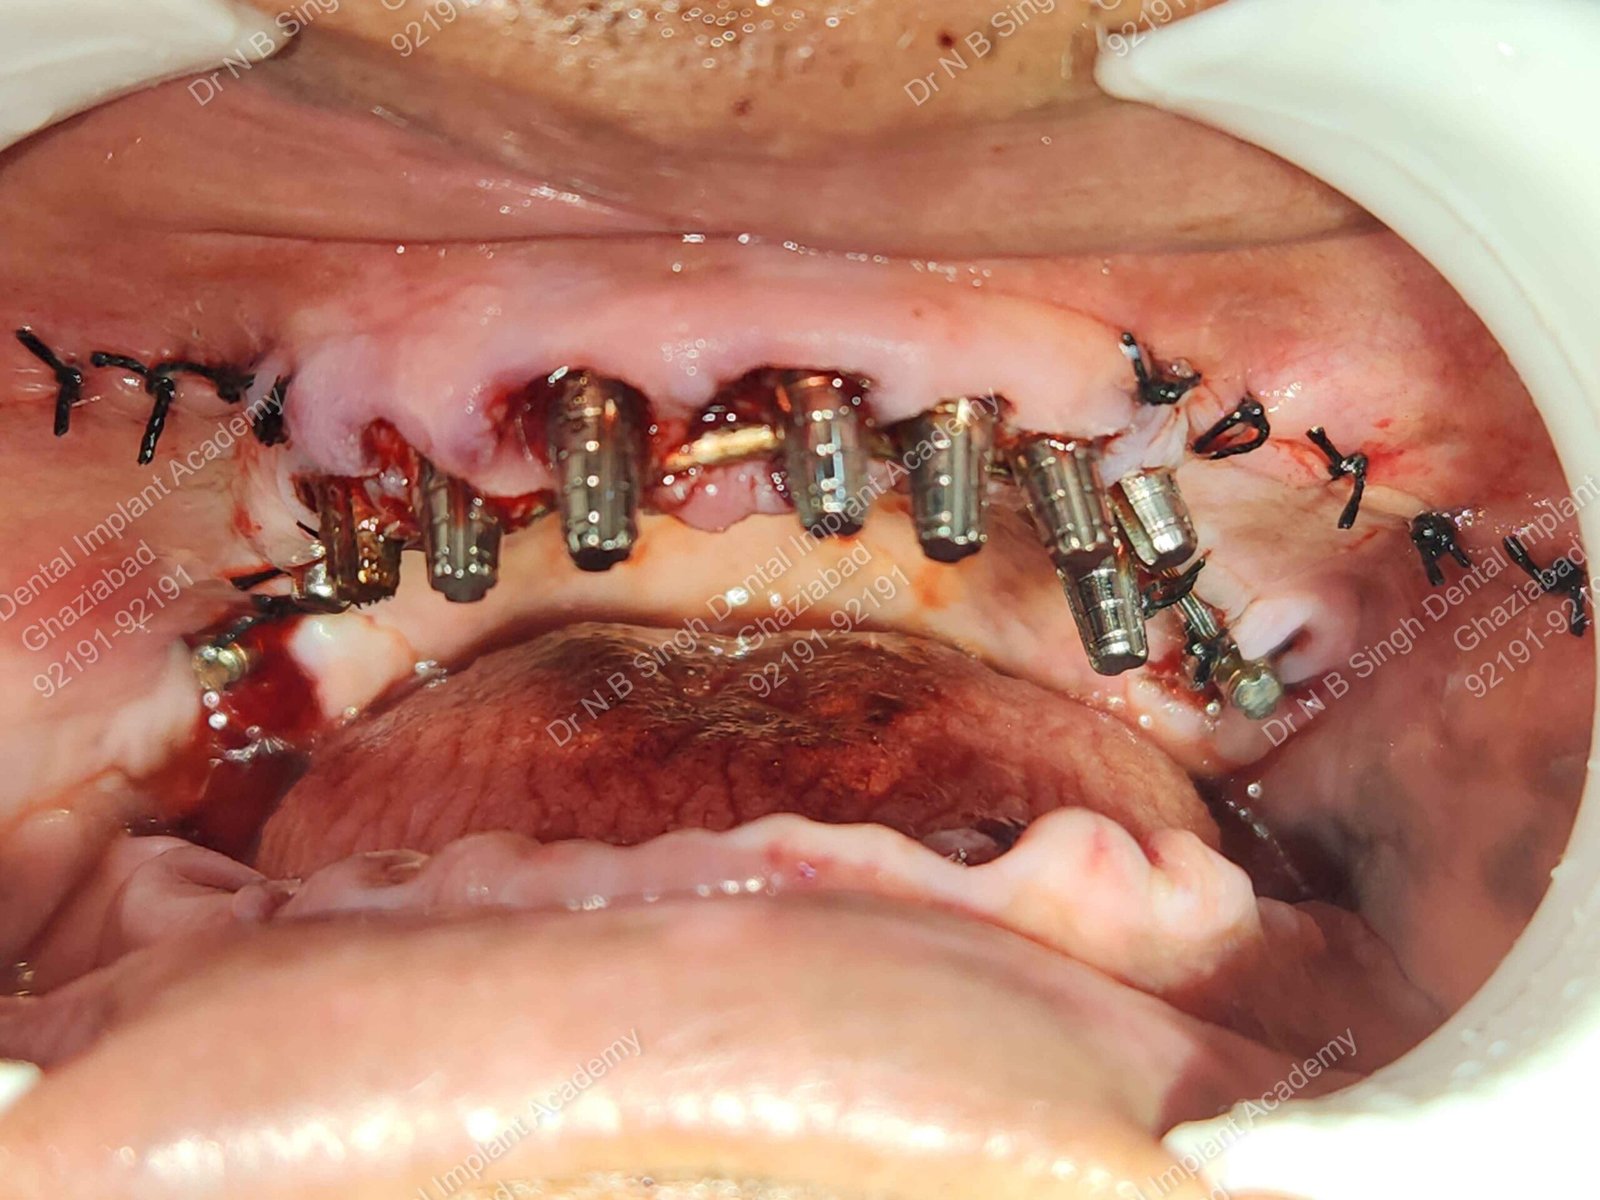

C1005 zygomatic basal implant full mouth – Ali Hasan 4

Dr. N.B. Singh